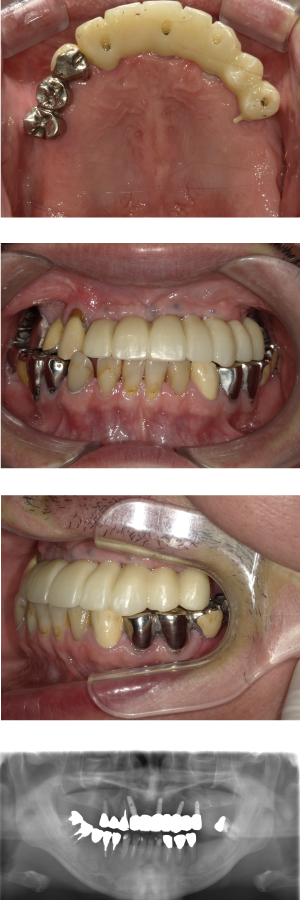

60代 女性 全顎 インプラント サイナスリフト等

| 年代・性別 | 60代・女性 |

|---|---|

| 主訴 | 上顎の入れ歯が割れた。リンゴやおかきを食べられるようになりたい。 |

| 部位 | 右上④3②・左上②3④5⑥のブリッジ |

| 治療期間 | 2年 |

| 費用 | ¥2,447,500(税込) |

| 副作用・リスク |

|